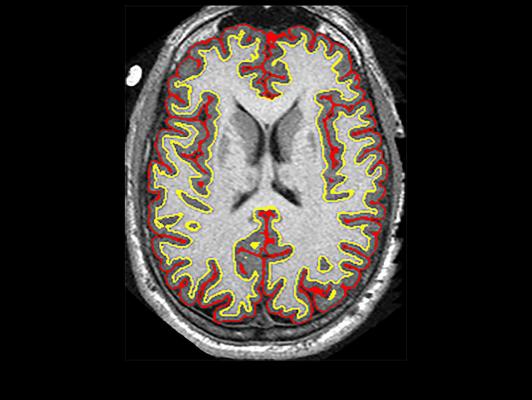

An NIH-funded clinical trial suggested that the anti-inflammatory drug ibudilast may slow brain shrinkage caused by progressive MS. Image courtesy of Robert J. Fox, M.D., Cleveland Clinic.

Robert J. Fox, M.D., a neurologist at Cleveland Clinic in Ohio, led a team of researchers across 28 clinical sites in a brain imaging study. They were investigating whether ibudilast was better than placebo in reducing the progression of brain atrophy, or shrinkage, in patients with progressive multiple sclerosis.

In the study, 255 patients were randomized to take up to 10 capsules of ibudilast or placebo per day for 96 weeks. Every six months, the participants underwent magnetic resonance imaging (MRI) brain scans. Fox’s team applied a variety of analysis techniques on the MRI images to assess differences in brain changes between the two groups.